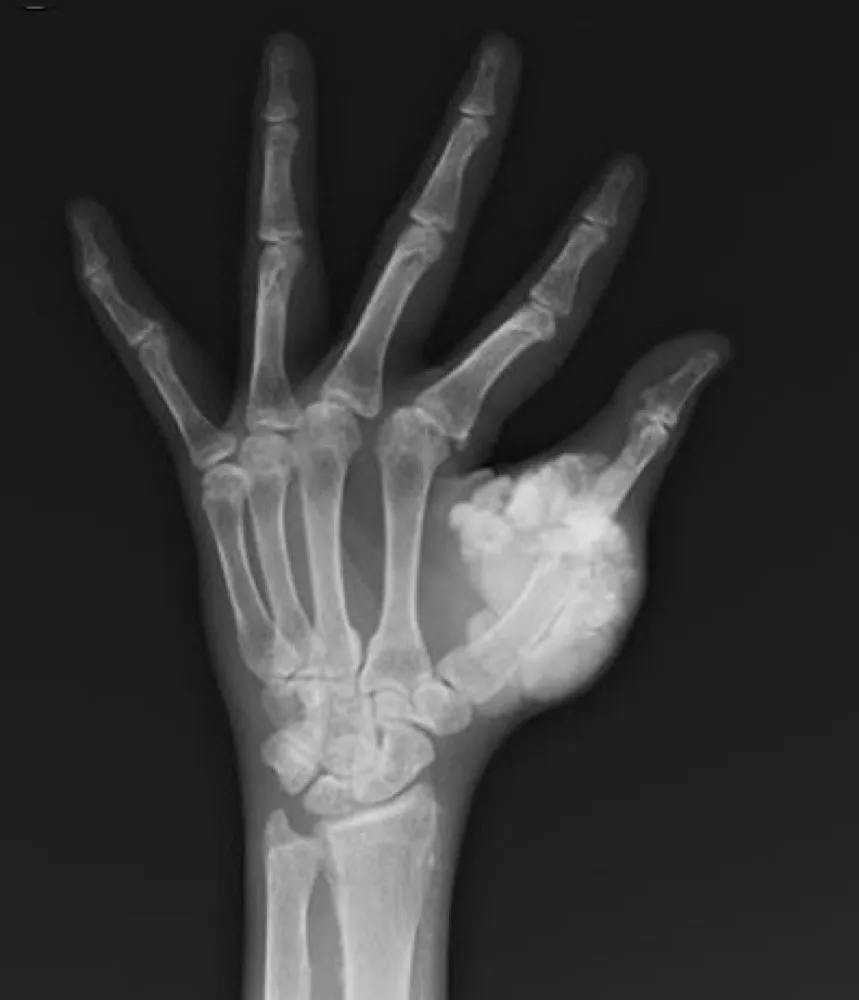

IRA + Icterícia: Um Caso que Exige Investigação Detalhada